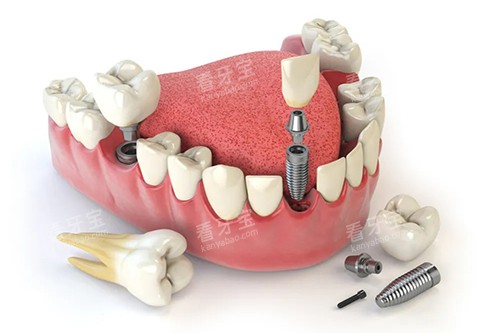

在种植牙方面,郑州植得口腔医院的种植导航系统是一大特色。

该系统利用计算机辅助设计和制造技术,结合患者的口腔 CT 数据,能够更好地规划种植体的位置、方向和深度。

在手术过程中,医生可以根据导航系统的指引,更加比较准地进行种植操作,减少手术创伤,缩短手术时间,提高种植成功概率。

同时,种植导航系统还可以模拟种植后的结果,让患者在手术前就能够直观地看到自己牙齿修复后的样子,增强患者的治疗信心。